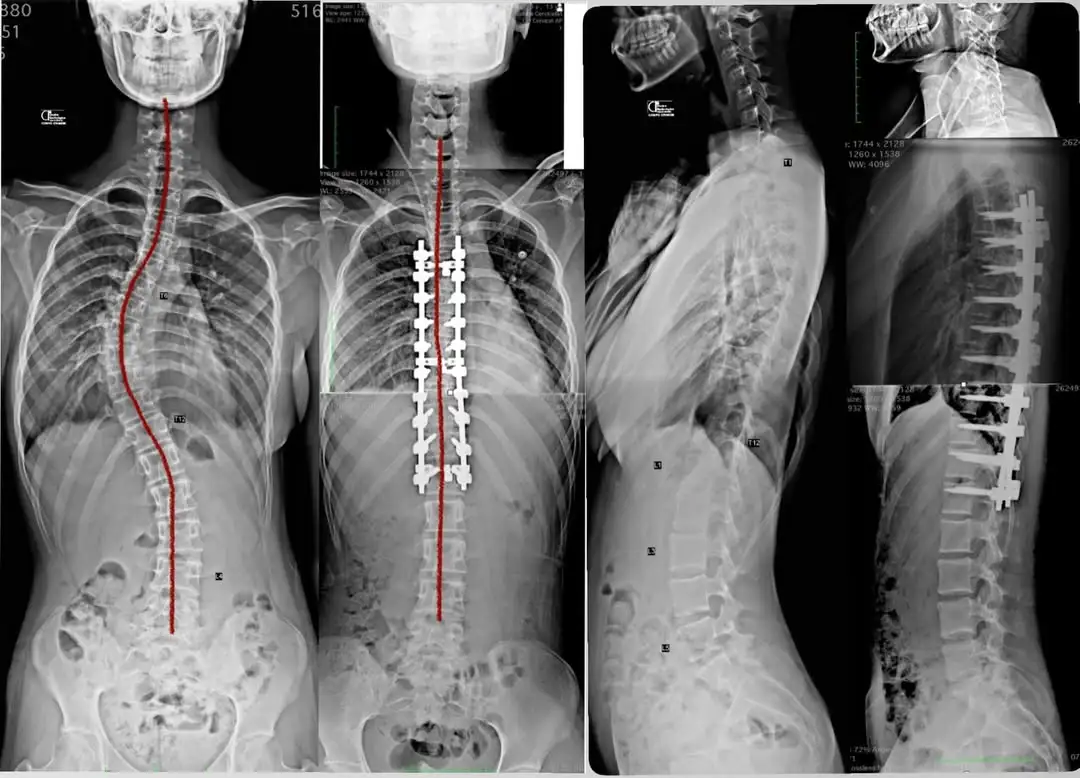

Neste primeiro caso (do vídeo acima), tratamos um adolescente com uma curva lombar grave (>60°). Porém, o fator crítico não era apenas o grau, mas a Translação Vertebral Apical.Imagine que o centro de gravidade do corpo é uma linha reta. Na escoliose com translação, a vértebra L4 estava deslocada lateralmente, longe desse centro. Isso cria uma “alavanca” perigosa. Se tentássemos economizar e parar a cirurgia na vértebra de cima (L3), deixaríamos a base (L4) instável e inclinada.A decisão estratégica: O risco aqui era o Adding-on. Esse fenômeno ocorre quando a cirurgia para “antes da hora”, e a gravidade continua empurrando as vértebras não operadas, fazendo a curva crescer novamente abaixo da cicatriz. Por isso, estendemos a fixação até L4, garantindo que a base da coluna ficasse paralela ao solo (horizontalizada) e totalmente estável. 👉 Entenda mais sobre a importância do alinhamento em nosso artigo sobre Obliquidade Pélvica.Caso 2: Artrodese Seletiva (Preservando a Lombar)

Agora, veja o outro lado da moeda. Nesta jovem paciente, a estratégia foi oposta: operar menos para ganhar mais.A escoliose estava progredindo rapidamente, mas a “personalidade” das curvas era diferente. Para entender isso, precisamos diferenciar dois conceitos:- Curva Estrutural (A Causa): No caso dela, a curva torácica era rígida. Ela era a “agressora” que desequilibrava o corpo.

- Curva Compensatória (A Reação): A curva lombar era flexível. Ela só existia porque a coluna tentava se equilibrar sozinha para manter a cabeça centralizada.

Optamos por uma Artrodese Seletiva. A ideia foi “atacar a causa” (fixando apenas a curva torácica rígida) e deixar a lombar livre. O resultado foi a autocorreção: assim que alinhamos o mastro superior, a base lombar, que ainda tinha discos saudáveis e móveis, se realinhou espontaneamente.O Resultado: Tratamos a deformidade preservando 5 vértebras lombares móveis. Isso significa que, no futuro, essa paciente terá muito mais facilidade para agachar, praticar esportes e realizar movimentos de torção do tronco, protegendo sua coluna contra o desgaste precoce.